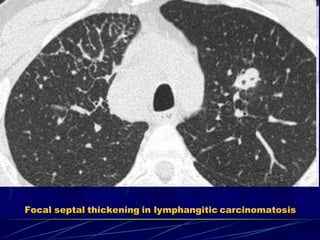

Focal septal thickening in lymphangitic carcinomatosis

Interlobular septal th. – lymphangitic carcinomatosis